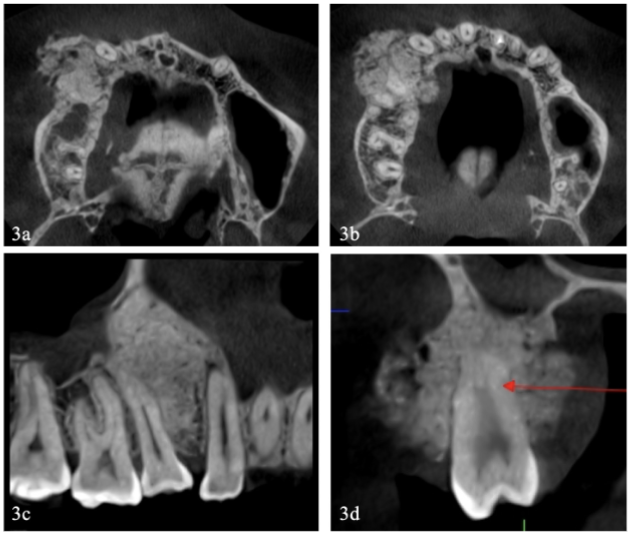

La TCHC proporcionó mayor información sobre las características imagenológicas de la lesión. En el corte axial de la maxila a nivel apical de las piezas de primer cuadrante, se observaba una imagen hiperdensa heterogénea con focos isodensos de forma ovoide y contornos irregulares que ocupaba el centro del reborde alveolar y se proyectaba hacia vestibular (figura 3 (a)). El corte axial a nivel de la parte media de las raíces de los dientes (figura 3 (b)) mostró una masa hiperdensa heterogénea de bordes regulares ubicada de distal de la pieza 13 a mesial de 16 que protruía hacia vestibular y palatino, su mayor tamaño estaba en vestibular. Comparativamente la densidad de la lesión era menor al de la cortical ósea y a la de la dentina (figura 2 (a y b)).

En el corte sagital se observaba una lesión hiperdensa con forma de pera invertida ubicada en distal de la pieza 13 y mesial de la pieza 15, se extendía desde la cresta alveolar hasta el piso del seno maxilar, en este nivel se notaba un espacio delgado isodenso que bordeaba a la lesión (figura 3 (c)). El corte transaxial mostraba un tumor de forma más o menos redonda hiperdensa con escaso focos isodensos adherido a la cara palatina y vestibular de la raíz de la pieza 15, en vestibular el contorno era marcadamente irregular debido a pequeñas proyecciones hiperdensas, de apariencia radial. Debido a los hallazgos tomográficos se decidió tomar una biopsia representativa de la lesión, cuyo resultado anatomopatológico fue cementoblastoma. Considerando el diagnóstico de cementoblastoma de pieza 15, con extensión hacia los dientes 13 y 16, el tratamiento quirúrgico consistió en la remoción en bloque del tumor incluyendo los dos dientes contiguos, siguiendo la técnica de maxilectomía parcial descrito como tipo II B por Brown et al., (17). Durante el acto quirúrgico se comprobó que el tumor expandía marcadamente la cortical vestibular comprometiendo la parte distal de la pieza 13 y mesial de la pieza 16 (figura 4 (a)).

Si bien el estudio de TCHC aportó mayor información sobre las características imagenológicas, el hecho de encontrar en los cortes axiales y transaxiales (figura 3 (a y d)), filamentos hiperdensos en la periferie del tumor reforzó la necesidad de asegurar un diagnóstico correcto de la lesión antes de proceder a su remoción quirúrgica, lo que se logró con la toma de una biopsia, la cual fue informada como cementoblastoma.